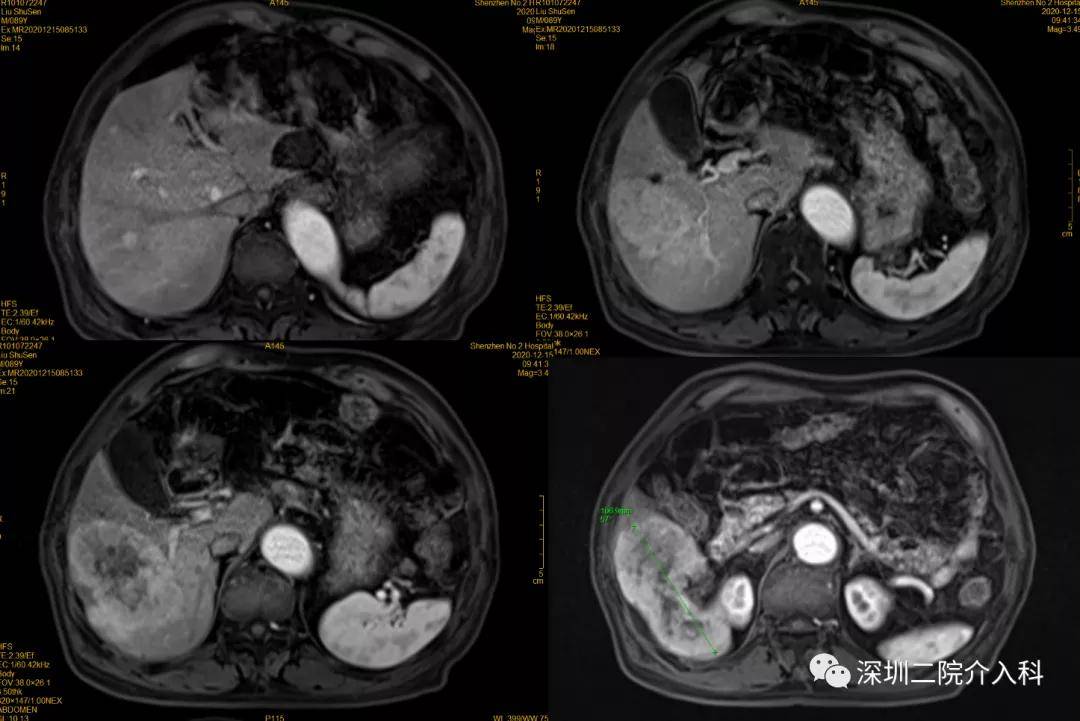

经过详细检查 , 患者甲胎蛋白升高 , 腹部MR增强示肝脏肿物 , 铅球样大小 。 诊断为原发性肝癌(BCLC B期) , 伴肝硬化 。

2020-12-15 术前MR增强

文章图片

2020-12-15 术前MR冠状位